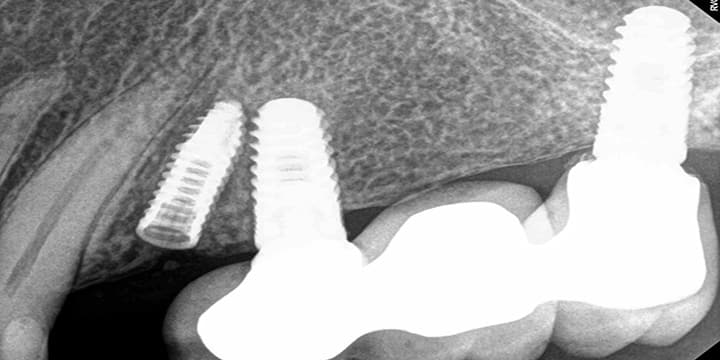

Dental Implant Placement in a Challenging Space

This case highlights Dr. XJamal's expertise in placing a dental implant in a particularly tight area. The "before" image shows the limited narrow apace available. The "after" image shows the seamless placement of the implant, restoring both function and aesthetics.